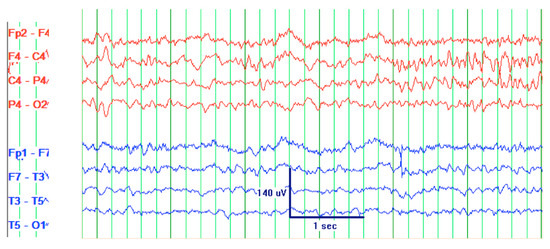

CT scan of the head was reassuring, showing no significant changes from the patient’s previous MRI, performed one month prior to this hospitalization. Unchanged lesions include: small inferolateral left temporal density, associated white matter low density, small medial right and left parietal occipital low densities, and a posterior cerebral white matter hypodensity (Figure 1). Patient’s EEG result read: abnormal EEG due to mild to moderate diffuse slowing, with excess low-moderate voltage polymorphic delta and theta activity (Figure 2).

Figure 1. Computed tomography (CT) head of a 61-year-old male with SCNS-DLBCL presenting with acute encephalitis. (a) CT Head shows a small area of inferolateral left temporal density, which correlates with the blood products that were seen in patient’s previous magnetic resonance imaging (MRI) associated with the temporal lobe lesion. There is associated white matter low density, which is similar to the non-enhancing signal on previous MRI; (b) CT Head shows a small area of medial left parietal occipital low density corresponds to the lesion and old blood seen on the MRI. It also shows a very small area of medial right parietal occipital low density corresponds to signal seen on the MRI.